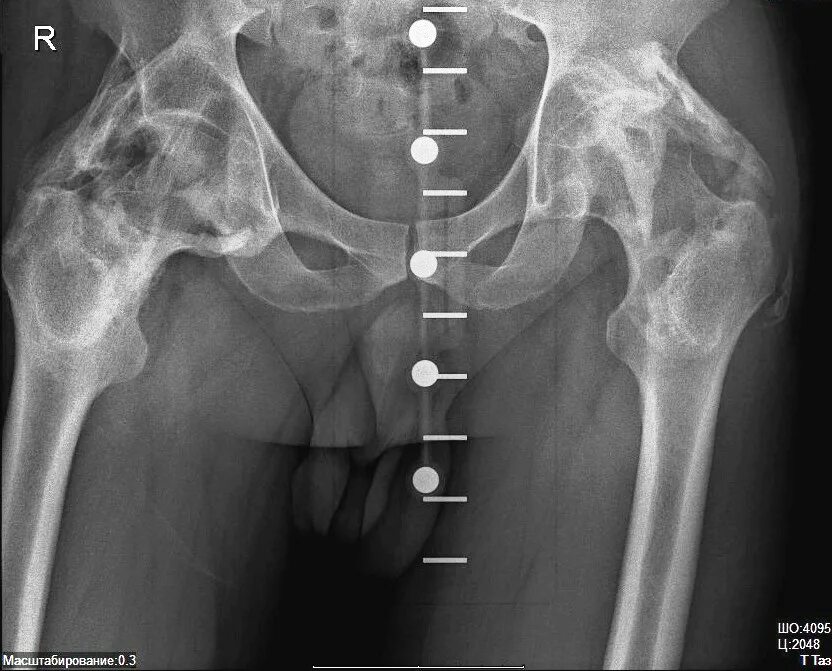

Анкилоз тазобедренного сустава